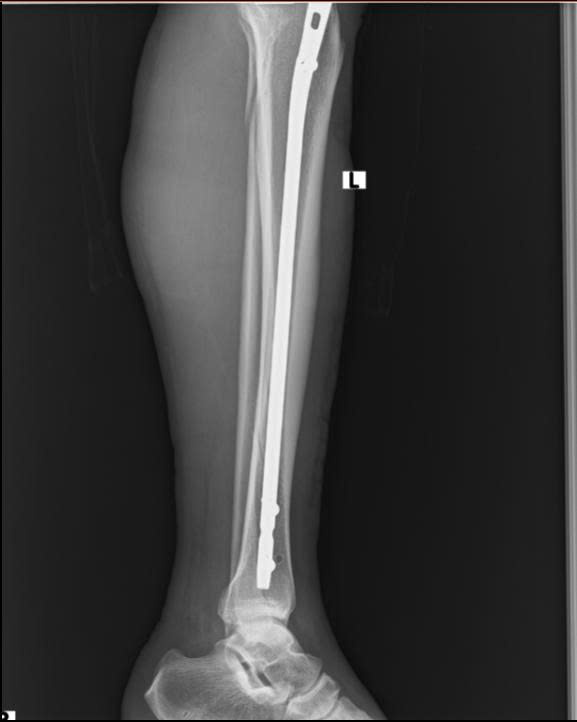

Hình ảnh: Xquang xương sau phẫu thuật

- Hình ảnh X-quang sau mổ cho thấy xương được nắn chỉnh và cố định vững chắc

- Sau 3 tháng, mức độ can xương vượt trội, tương đương mổ mở sau 6 tháng – chứng minh hiệu quả vượt trội của kỹ thuật